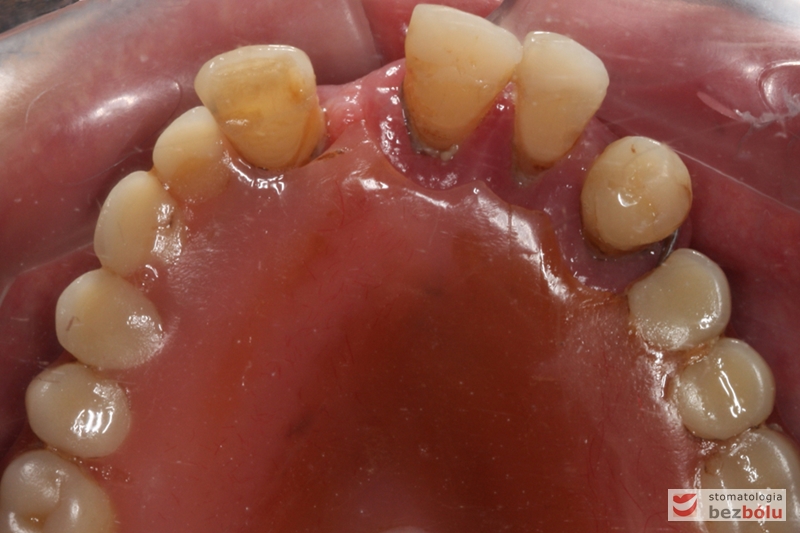

Widok łuku górnego przed leczeniem

Stan wyjściowy - bez protez, liczne braki zębowe i po 2 nierokujące zęby w szczęce i żuchwie

Stan wyjściowy – bez protez, liczne braki zębowe i po 2 nierokujące zęby w szczęce i żuchwie